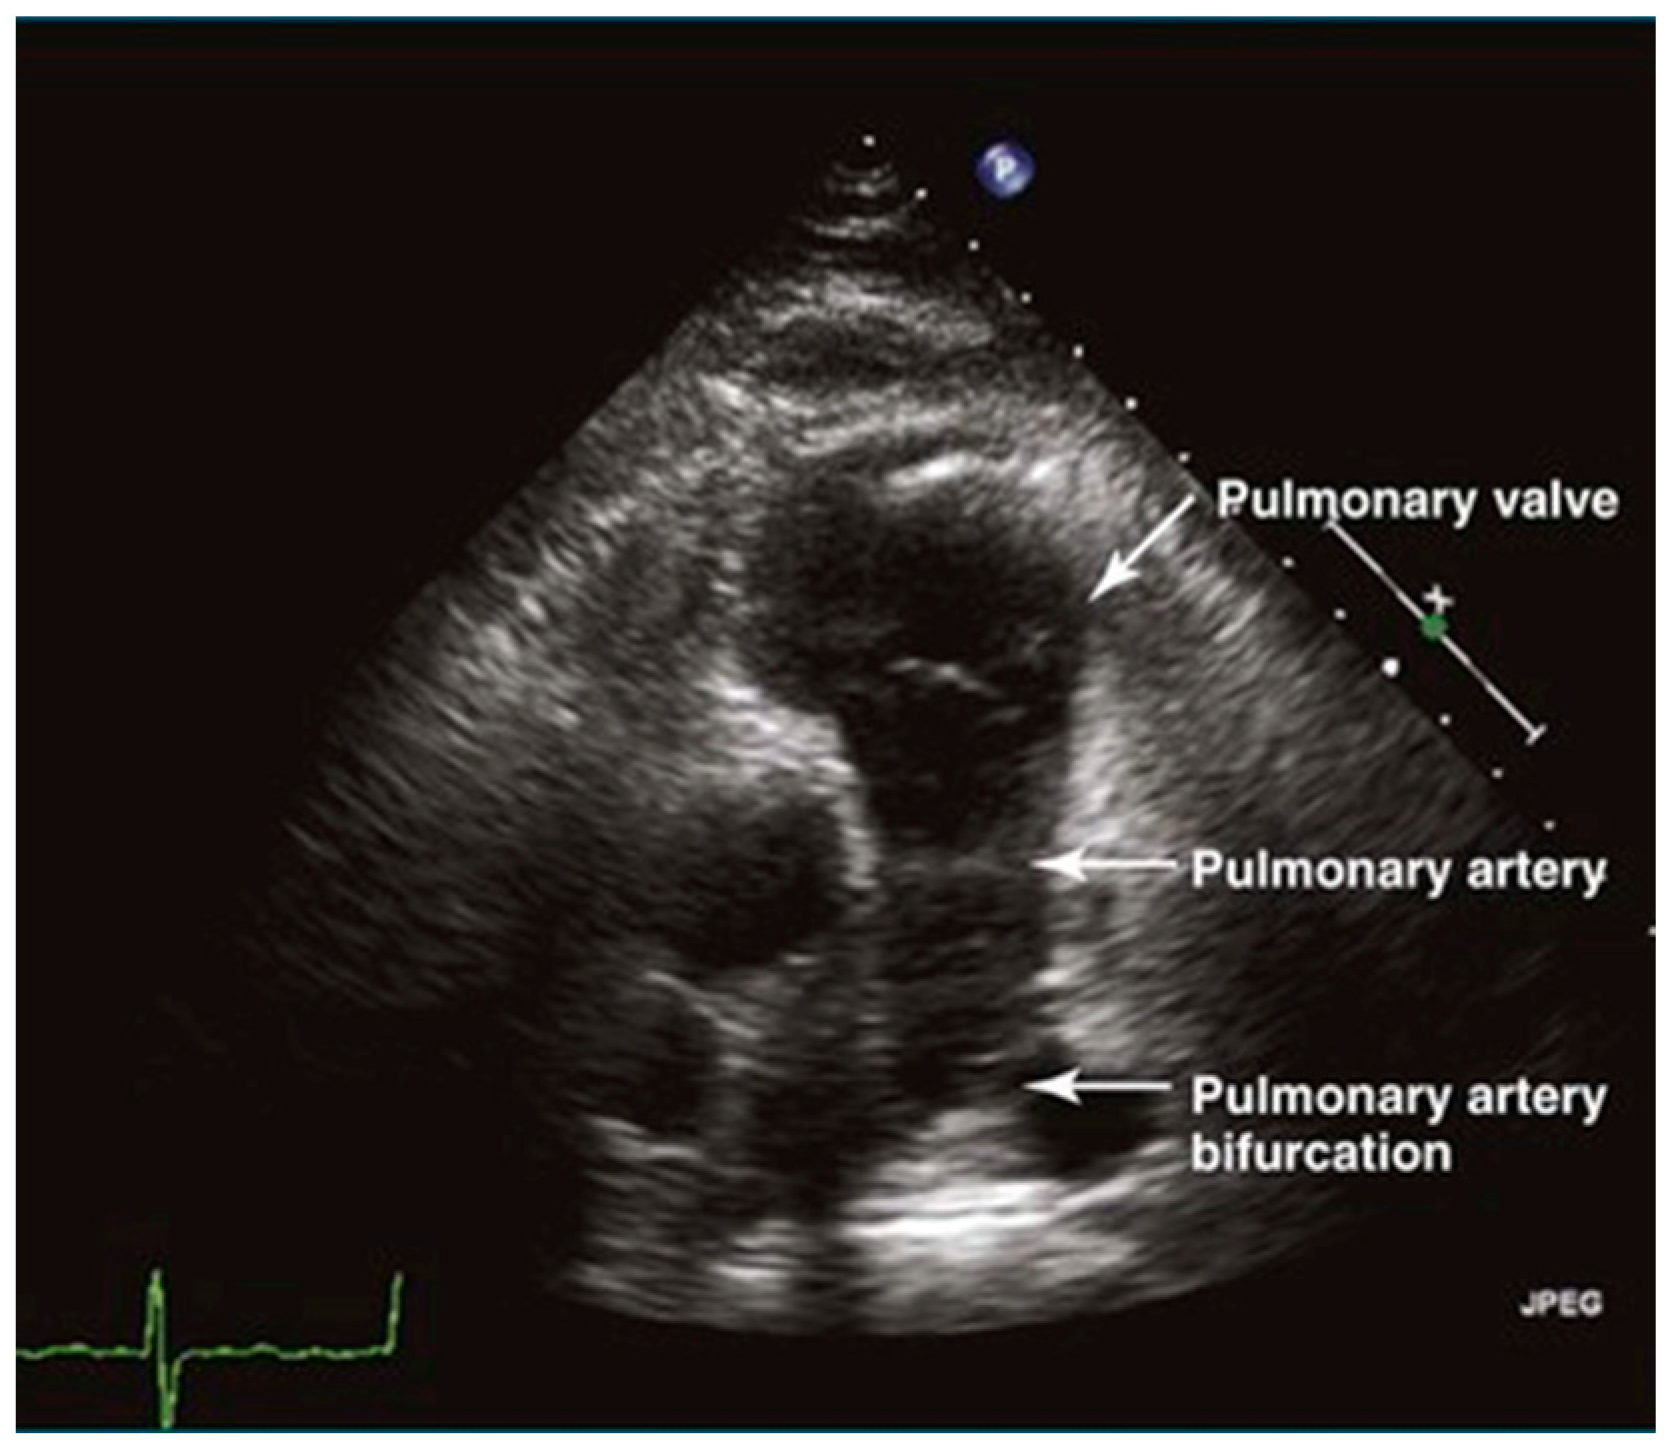

3.1.3. Pulmonary Artery

The long-axis view of the pulmonary artery shows the main pulmonary artery and its branches, aiding in the identification of space-occupying lesions like thrombi (Figure 5). This view is crucial for diagnosing acute pulmonary embolism. Additionally, the width of the main pulmonary artery helps differentiate between acute and chronic pulmonary hypertension, with significant widening indicating the chronic form [14].

Figure 5.

The sign of pulmonary artery in long-axis view.

Physicians can assess pulmonary artery pressure quantitatively with point-of-care ultrasound. According to Bernoulli’s principle, the systolic pressure and diastolic pulmonary artery pressure can be estimated, respectively, by measuring the maximum regurgitation velocity of the tricuspid valve and the pulmonary valve. The maximum regurgitation velocity of the tricuspid valve (TVR Vmax) can be measured in the apical four-chamber view (Figure 6), and the maximum velocity of the pulmonary artery valve regurgitation (PVR Vmax) can be measured in the pulmonary artery long-axis view (Figure 7). Physicians can estimate pulmonary artery systolic pressure (PASP), diastolic pressure (PADP), and mean pulmonary artery pressure (mPAP) based on the ultrasound-measured TVR Vmax and PVR Vmax by the following formulas: